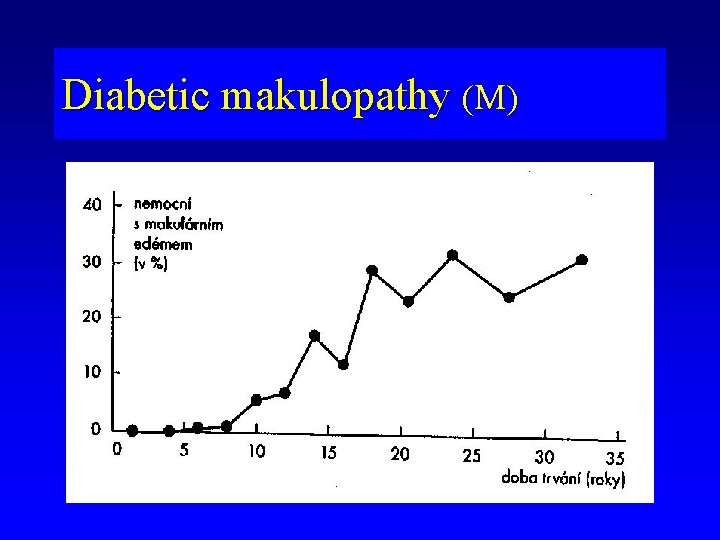

Diabetic makulopathy (M)

Diabetic maculopathy (M) • affects 33% of diabetic patients after 8 -10 years of duration of disease • the most common cause of vision loss in diabetic retinopathy